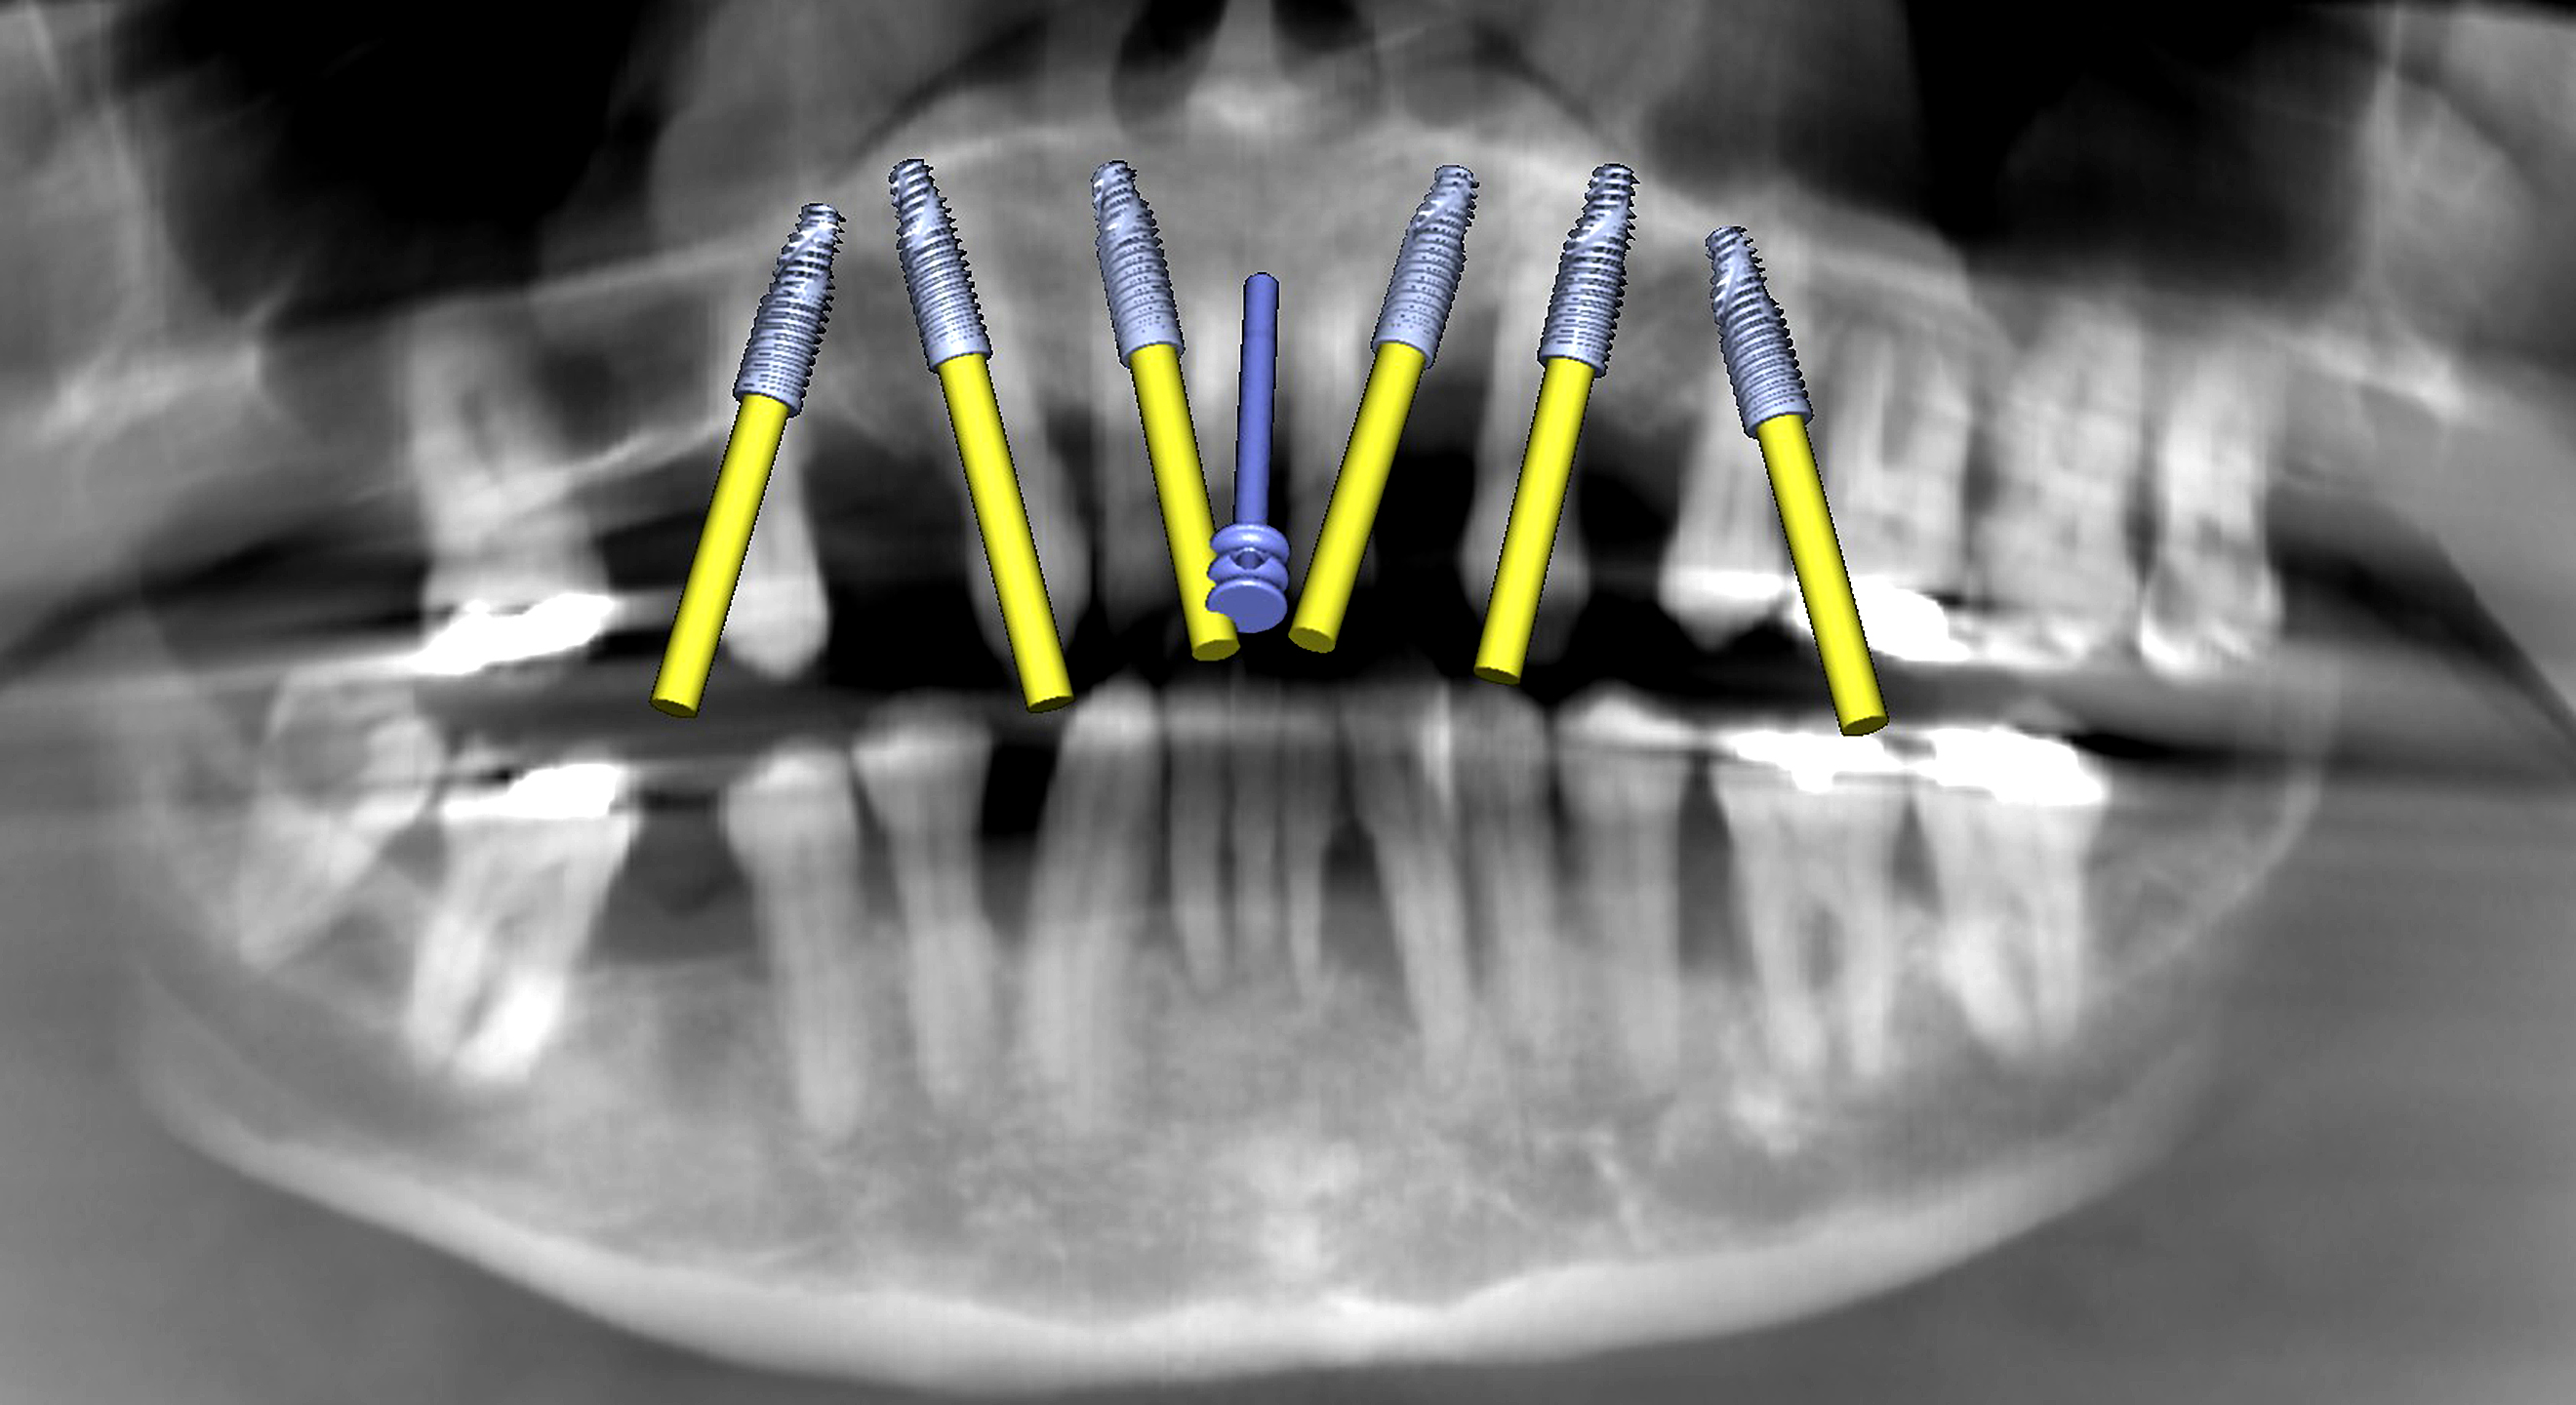

Fig. 2a: Pre-op panoramic radiograph showing extensive bone loss.

Fig. 2b: Maxillary implant simulation on the panoramic radiograph showing six implants and a nasopalatine canal pin.

The initial plan for the maxillary arch was to remove all the remaining natural teeth, place six implants and employ bone grafting material where necessary to fill the sockets and other concavities or fenestrations. The simulated implants were visualised on the panoramic reconstruction, including an anchor pin located at the midline engaging the nasopalatine canal (Fig. 2b). Using advanced features to distinguish between objects based on their radiodensity, interactive treatment planning software (Blue Sky Plan) and user-defined selective transparency, the simulated implants could be fully appreciated within a 3D rendering of the maxillary bone (Figs. 3a–c).